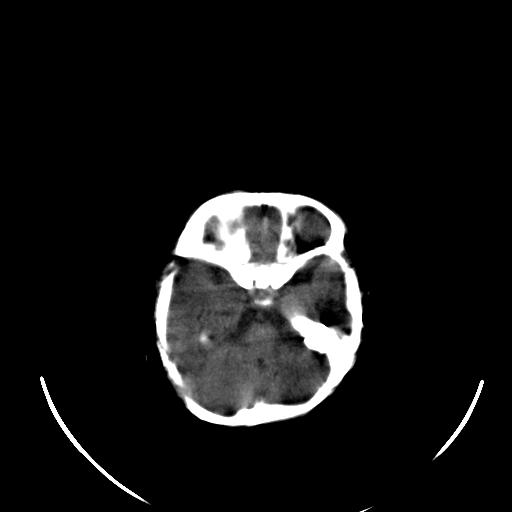

患儿 女性 1个月  今天发现阵发性抽搐  双眼上翻、凝视,嘴唇及面色青紫

考虑双侧脉络膜裂囊肿。

双侧颞枕叶片状低密度影,考虑新生儿却血缺氧性脑病可能

左侧额叶见班片样低密度灶,症状像癫痫,可能与之有关。

新生儿却血缺氧性脑病不排除!

左侧额叶见班片样低密度灶,建议mr

考虑hie。

考虑新生儿hie。